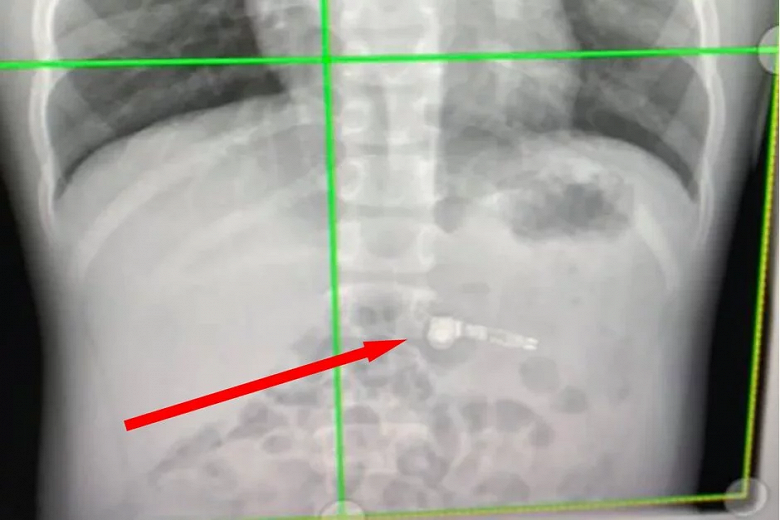

Мама рассказывает, что ее ребенок просто держал один наушник во рту за длинную часть, а потом проглотил, при этом она не успела отреагировать. Специалисты в отделе охраны здоровья детей Атланты были озадачены этим обстоятельством, обнаружив на рентгеновском снимке один из наушников AirPod.